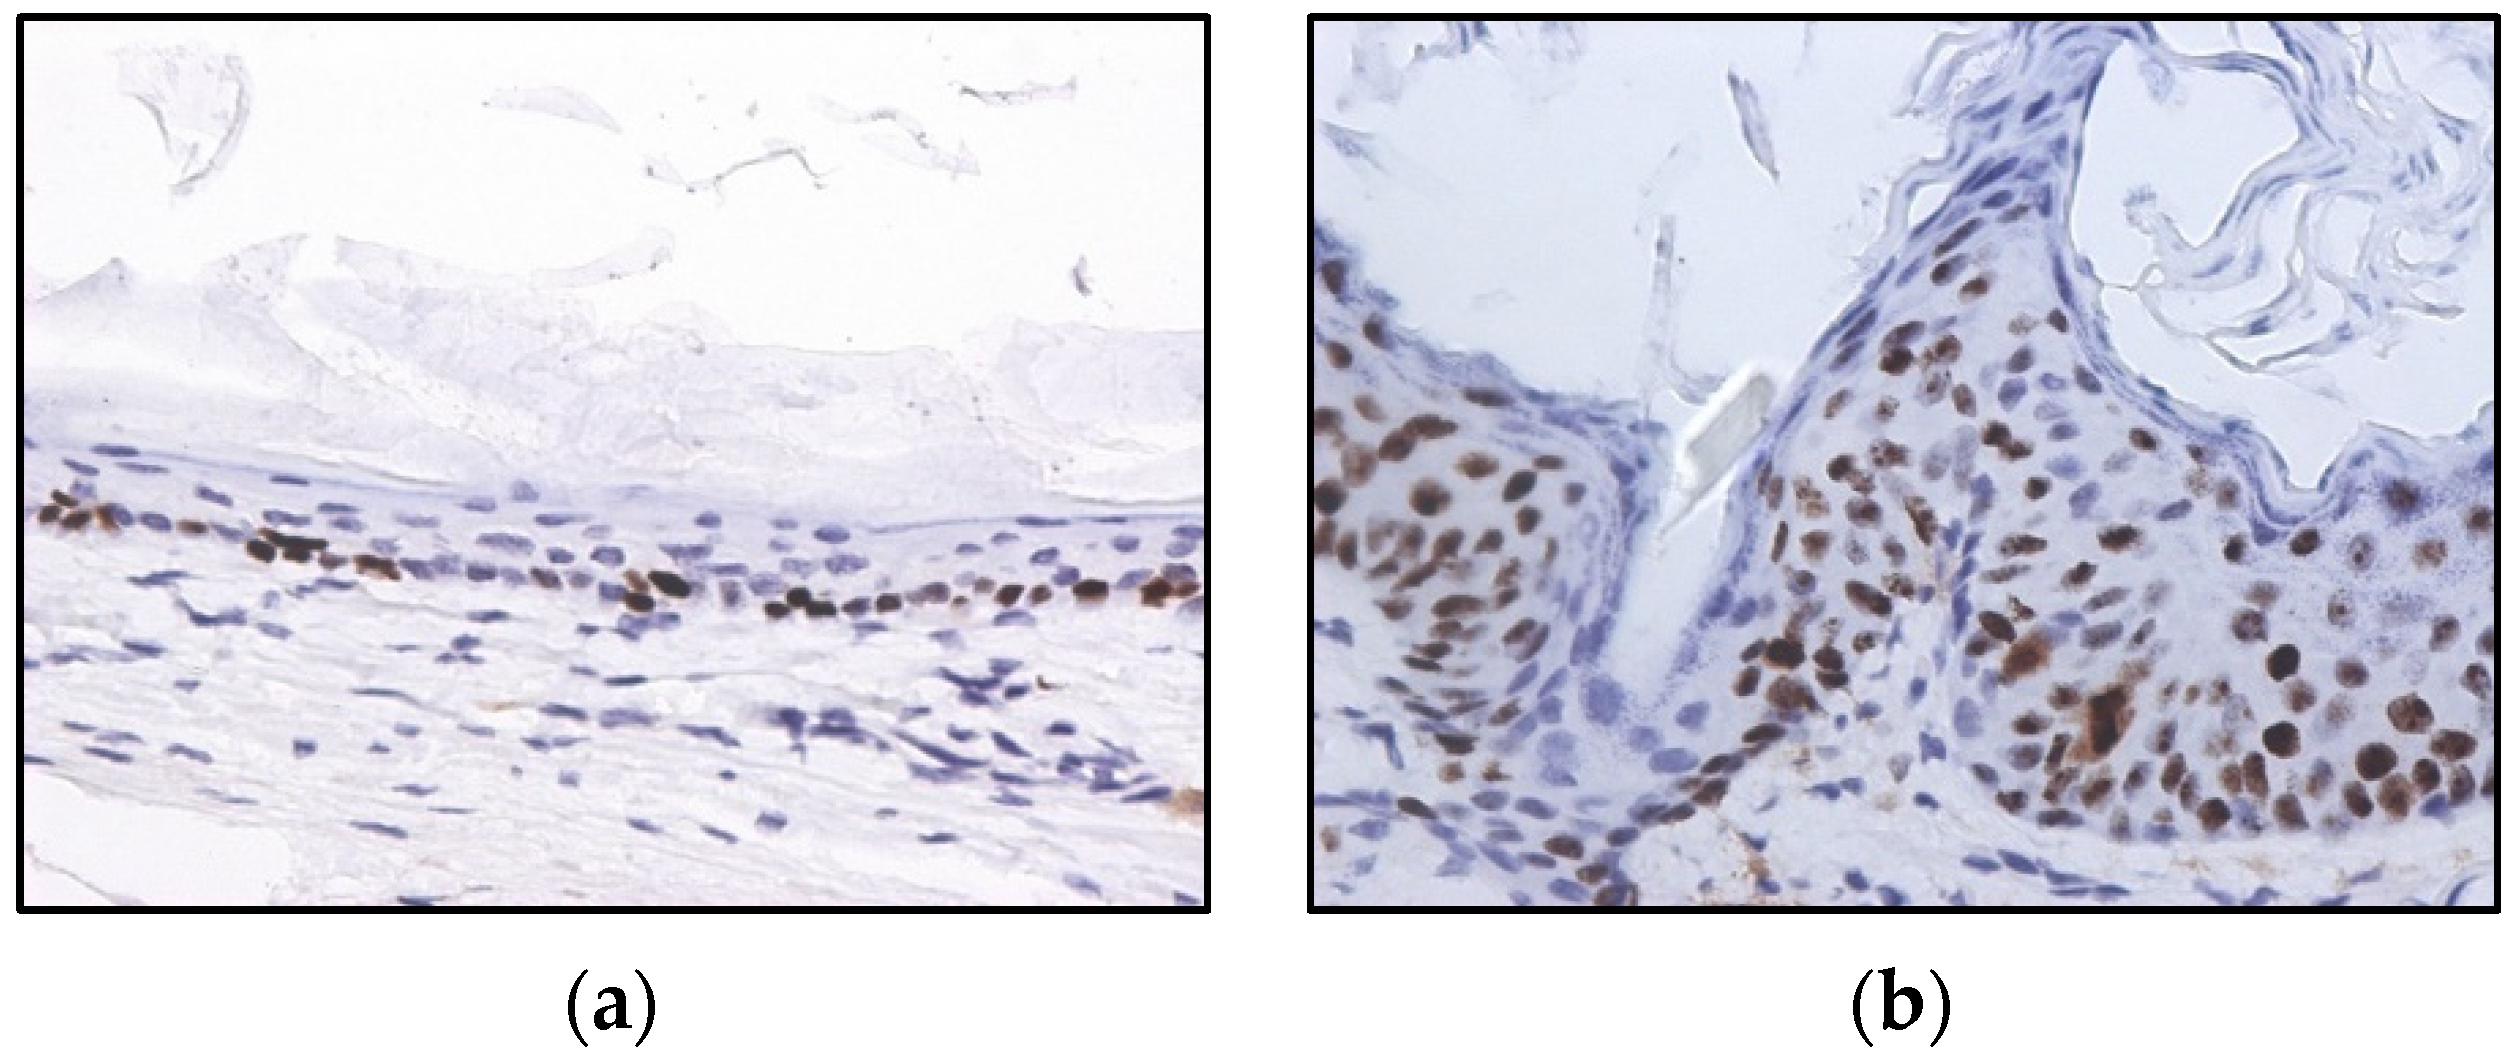

All ear and chest skin samples from wild type animals (groups I and II) showed normal histology (Figure 3 and Table 2). HPV16-negative animals showed a physiological distribution of proliferating epidermal cells with basal layer restricted Ki67 positive cells (Figure 4a).

Figure 4.

Immunohistochemistry for Ki67, in wild-type (a) and HPV16-transgenic (b) mouse skin. In panel (a), Ki67-positive cells are restricted to the basal epidermal layer. In panel (b), Ki67-positive cells are scattered through all epidermal layers, reflecting HPV16-induced aberrant proliferation. 3,3’-diaminobenzidine (DAB)–Mayer’s hematoxylin, 400×.

All ear and chest skin samples from wild-type animals (groups I and II) showed normal histology (Figure 3 and Table 2). HPV16-negative animals showed a physiological distribution of proliferating epidermal cells, with Ki67-positive cells restricted to the basal layer (Figure 4a). On the other hand, the epidermis of HPV16-transgenic animals showed Ki67-positive cells in suprabasal layers (Figure 4b), reflecting unchecked cell proliferation, as expected. Untreated transgenic animals (group IV) showed epidermal hyperplasia (100% incidence), and 63.4% also showed multifocal to diffuse epidermal dysplasia in both the ears and the chest. Parecoxib-treated HPV+/− mice (group III) showed a 100% incidence of dysplasia, but dysplastic lesions were absent in all mice (p = 0.027 versus untreated, group IV). HPV-transgenic mice showed increased numbers of tumor-associated leukocytes compared with wild-type animals (Figure 5). Parecoxib reduced leukocytic infiltration in HPV-induced lesions (Figure 5).

4.4. Immunochemistry

The skin samples were tested immunohistochemically for expression of the proliferation marker ki67. Briefly, endogenous peroxidase was blocked using Refine Peroxide Block (Leica) and the slides were incubated with the primary antibody (D3B5, Cell Signaling, 1:1000) for 60 min. The refine (rabbit) polymer HRP (Leica) was used as secondary antibody and the antibody reaction was detected with 3.30-diaminobenzidine tetrachloride (DAB) for 10 min and counterstained with Mayer’s hematoxylin (4 min). Mouse spleen samples were used as positive controls and mouse IgG was used as an isotype control. Samples were classified as normal when ki67-positive cells were restricted to the basal layer of the epidermis or as pathological when suprabasal layers showed positive cells as well.